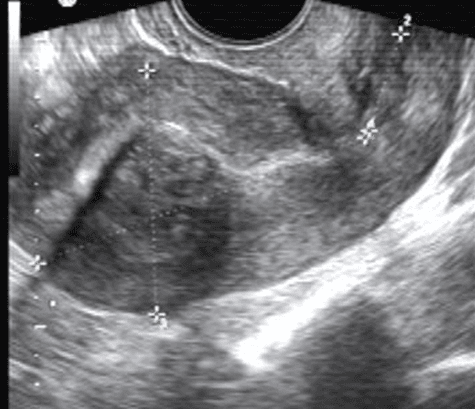

U xơ cơ tử cung dưới niêm mạc lâm sàng thường gây rong kinh, rong huyết

U xơ cơ tử cung trong cơ, u giảm âm do thành phần cơ nhiều hơn xơ trong u